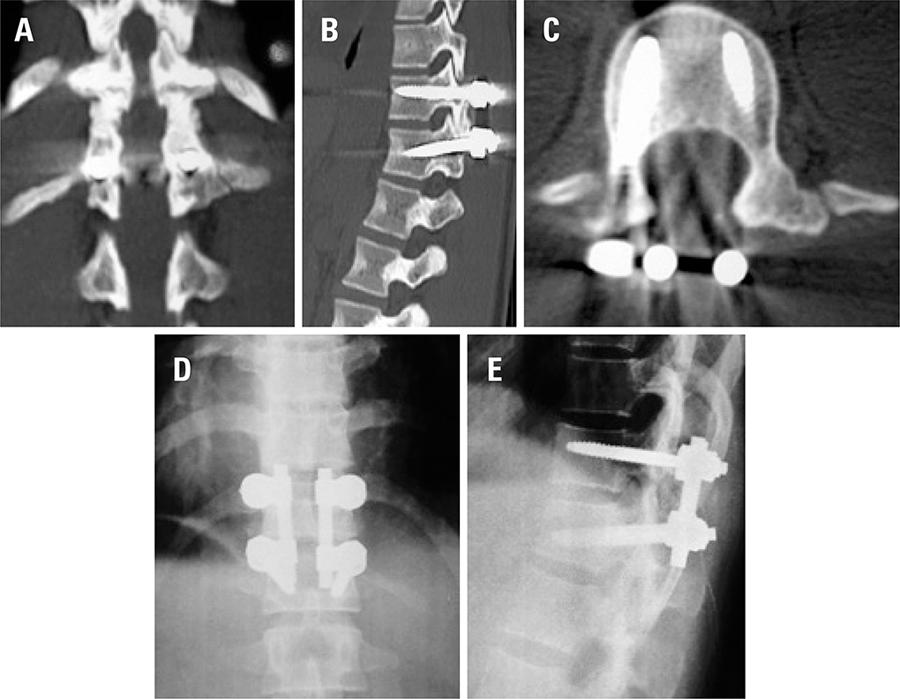

Relatamos um caso raro de fratura instável da coluna vertebral com envolvimento ligamentar, ocorrida por mecanismo de flexão-distração, durante jogo de futebol feminino profissional. Não houve déficit neurológico. A paciente apresentava espaçamento doloroso dorsal na linha média, que sugeriu lesão ligamentar, a qual não foi reconhecida imediatamente. Apesar disso, realizaram-se imobilização adequada e encaminhamento para unidade hospitalar, fatos que evitaram a ocorrência de danos adicionais à medula espinal. A paciente foi submetida à fusão monossegmentar, com instrumentação e, após 6 meses, retornou à prática de futebol profissional. O presente estudo alerta para a possibilidade de ocorrência de lesões graves e instáveis na coluna durante a prática de futebol, e para importância da assistência inicial adequada ainda em campo, a fim de evitar lesões neurológicas iatrogênicas.